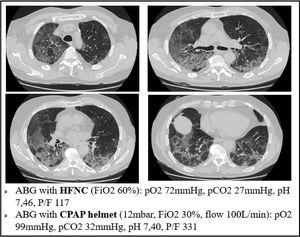

Our findings suggest that the injured areas of the lung are regions with high blood perfusion and rather normal alveoli, therefore in these areas the V/Q ratio reaches the lowest values. Prone positioning leads to a blood flow redistribution to the less damaged area, and hence to a new balance of the V/Q ratio, increasing arterial oxygen levels (Fig. 3)

This mechanism is well represented in Fig. 4, a 49yo male with no past medical history. The CT scan was obtained after 9 days from the onset of symptoms, and displays the typical radiological findings of SARS-CoV-2 pneumonia, mainly in the dorsal region of the lungs. Visual severity score was 12/20. This was one of the patients that underwent lung biopsy. Lung tissue from the altered region of the right lower lobe showed areas of high blood flow, due to capillary hyperplasia and venous dilation, surrounding patent alveoli. Switching the patient to the prone position resulted in a rapid improvement in arterial blood oxygenation at ABGs.